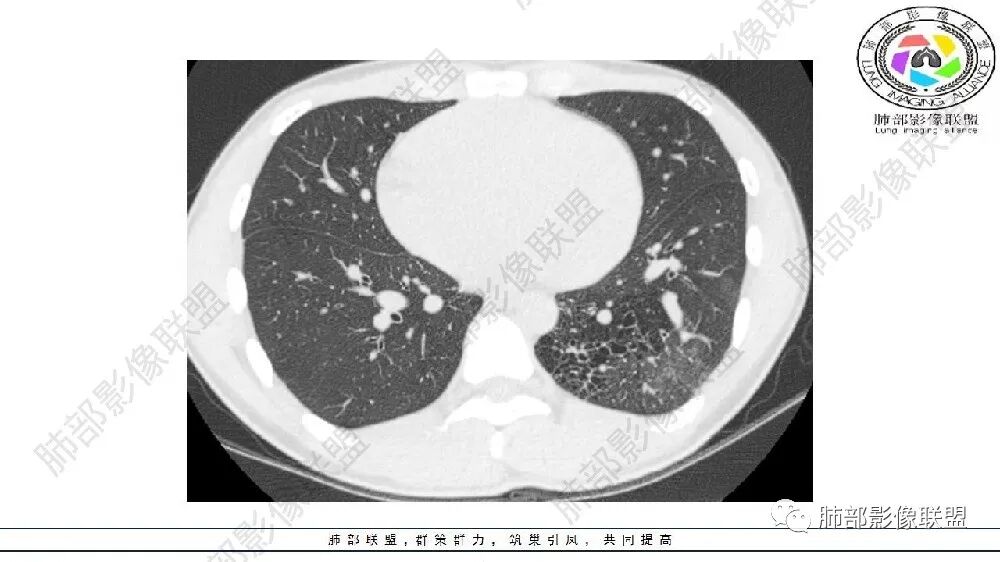

左肺下叶多发大小不等囊腔,周围伴有磨玻璃影,考虑CCAM伴感染。

左肺下叶多发大小不等囊腔伴周围磨玻璃影,可见血管增粗,似与胸主动脉相连,考虑肺隔离症,鉴别CPAM。

左肺下叶多发大小不等囊腔,囊壁略厚。周围见片状高密度影,边缘模糊不清,考虑CCAM伴感染,鉴别隔离症

左肺下叶多发囊腔、结节,及磨玻璃密度影,考虑肺隔离症,鉴别CCAM

左肺下叶多发大小不等囊腔,部分有粘液栓,周围伴有磨玻璃影,左肺下叶基底干支气管未见,双肺尖可见多发局限性透亮区,青年男性,考虑先天性气道或肺部发育畸形,支气管闭锁?CPAM?鉴别肺隔离症。

左肺下叶大小不等含气囊腔,壁厚薄不均,粘液栓,考虑 ccam,鉴别支气管闭锁,肺隔离征。

左肺下叶多发薄壁囊性病灶,血管贴边,并多发增粗的血管,还有一些斑片影,磨玻璃影;两肺尖也有薄壁囊性病灶;病史咳嗽咳痰,痰中带血,跟老师们考虑肺隔离症伴感染,鉴别LIP

患者年纪小,考虑先天发育性疾病,多发大小不等薄壁囊腔影,有实性结节,囊腺瘤样畸形或者肺隔离症(左下肺后基底段),增强扫描有无体循环供血

左肺下叶多发囊腔,粗大血管影,隔离征可能,鉴别气道畸形。

常规思路: 20岁,肺部出现低密度病灶:多半要考虑先天性病变;其次就是坏死空洞。先天性:肺气肿、囊腺瘤样畸形、闭锁、隔离、支气管扩张,这些病灶符合肺气肿,低密度,胸膜下,无壁。

这些有高密度影,有痰中带血,首先警惕感染或支气管动脉破裂出血(多见于支气管扩张)

可见囊状影、管状影,附近血管明显增粗,似乎与肺动脉不相连

闭锁?附近没有大片肺气肿,不符合。为啥没有一元论?因为上肺病灶与左下叶病灶表现完全不同,一个是单纯低密度影,无壁;一个是管状+血管畸形